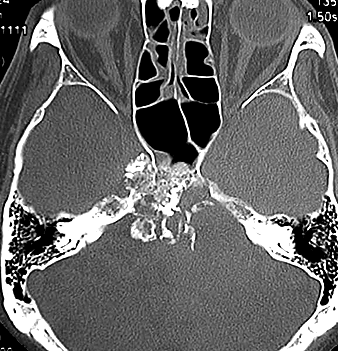

左動眼神経麻痺が急速に進行した例です。斜台から左海綿静脈洞,錐体骨尖を侵す頭蓋底軟骨肉腫です。左内頚動脈は腫瘍に取り囲まれています。

CTでは腫瘍実質部分が増強されます。不規則な骨破壊像・浸食像が特徴的です。

骨軟骨腫 osteochondroma の悪性化例:secondary chondrosarcoma

骨軟骨腫が若い時からあって壮年になってから悪性化した軟骨肉腫です。20代のときに右外転神経麻痺が生じて20年以上そのまま経過しました。左のCTでは頭蓋骨の真ん中の斜台というところに異常な骨があって,良性の骨軟骨腫のように見えます。でも右側のMRIでは脳幹部に深く食い込む柔らかい腫瘍の部分が写っていてこれは軟骨肉腫を疑う像です。手術摘出と術後の放射線治療をしました。